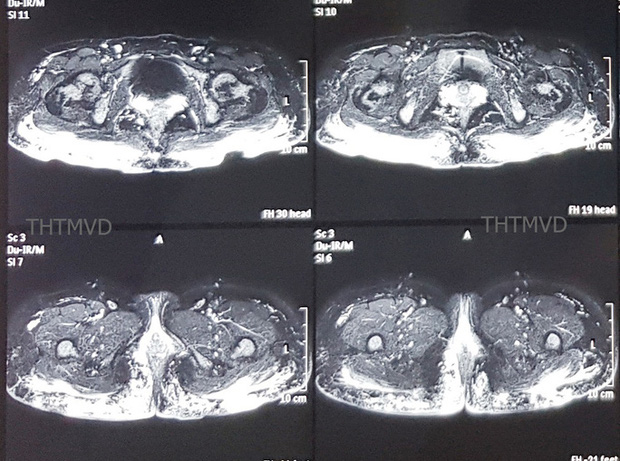

Trên phim chụp cộng hưởng từ cho thấy hàng trăm khối u siliconoma (sau bơm silicone bạch cầu gom lại thành khối) cùng hiện tượng viêm lan tỏa trong lớp da cơ mông và thâm nhiễm cả đến gần hậu môn. Đáng nói là khi cấy mủ vùng mông, các bác sĩ phát hiện bệnh nhân đã bị nhiễm loại vi khuẩn đa kháng thuốc, kháng hầu hết các loại kháng sinh thông thường.